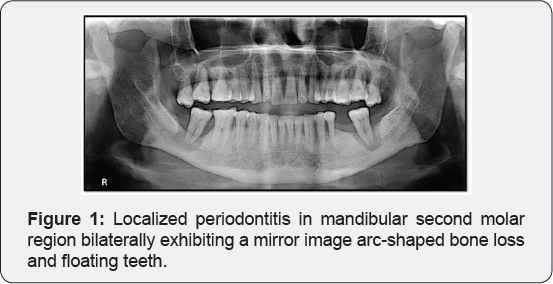

A 45-year-old male patient reported to our department with a chief complaint of pain and a mild swelling in the right side of the face since 2 weeks. The patient gave a history of a dull aching pain, intermittent in nature since 2 weeks and an associated swelling and a progressive restriction in mouth opening since 1 week. A thorough intra-oral examination was not possible as the mouth opening was extremely limited. Since an IOPA was not possible ailing to the above mentioned reason, a panoramic radiograph was advised. The radiograph revealed an arc shaped bone loss extending from distal to first molar to mesial of third molar region and a floating second molar, both features seen as a mirror image bilaterally (Figure 1). A final diagnosis of localized aggressive periodontitis was established and patient was advised for extraction of the mandibular second molars followed by periodontal and prosthetic evaluation.

These infra-bony pouches can lead to compromise of the furcation and cause mobility in permanent teeth [3]. Aggressive periodontitis can be classified as localized and generalized. The localized form is characterized as to affect first molars and permanent incisors, with loss of supporting alveolar bone and the generalized in no more than two teeth other than first molars and incisors which is not as in our case [4]. Radiographic findings may include an ‘arc-shaped’ loss of alveolar bone extending from the distal surface of the second premolar to the mesial surface of the second molar. Bone defects are usually wider than usually seen with chronic periodontitis.

Frequently, bilaterally symmetrical patterns of bone loss results forming a 'mirror image pattern' as witnessed in our case [5]. Early detection is critically important in the treatment of aggressive periodontitis for preventing further destruction is often more advocated than attempting to regenerate lost supporting tissues. One of the most important aspects of treatment success is to educate the patient about the disease, including the causes and the risk factors for disease, and to stress the importance of the patient's role in the success of treatment [6].